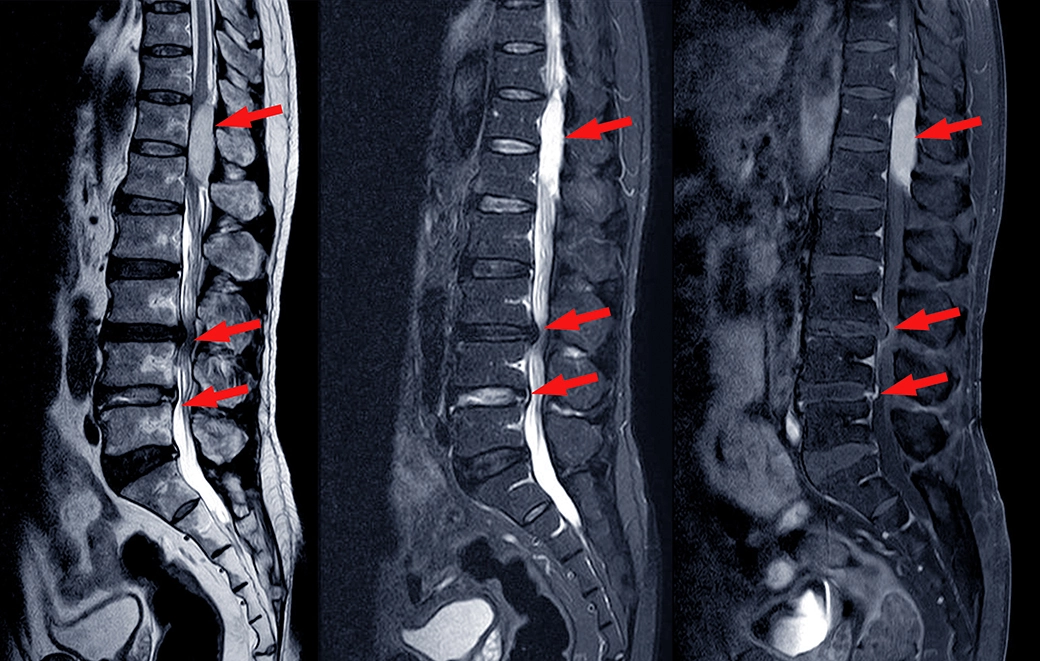

As you may know, spinal stenosis involves a narrowing of the openings in the spinal column through which your spinal cord passes. In the case of lumbar spinal stenosis, it involves the narrowing of the actual spinal canal in the lower back. In the case of cervical spinal stenosis, it involves the neck.

Another similar condition, foraminal stenosis, involves the narrowing of the foramen, the openings through which nerves exit the spinal column. Although it is a different condition, there are similar conservative treatments for foraminal stenosis, as well.

As mentioned above, when I discussed physical therapy, a misaligned spine can aggravate a case of spinal stenosis making it more painful than it need to be. This is because, if the individual holes that make up the spinal canal are not aligned with each other, the spinal cord will, necessarily, have a smaller cross-section to pass through when traversing sections that are out of alignment. Hence, the spinal cord is more likely to be impinged upon. This creates greater pain and discomfort and can lead to greater disability.